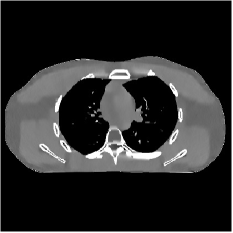

We pre-learned two transforms (Fig. 1) for the proposed two-layer model from image patches extracted from five XCAT phantom [24] slices, with , , and a patch extraction stride . We ran iterations of the learning algorithm in Section 3.1 to ensure convergence. We simulated 2D fan-beam CT test scans using XCAT phantom slices (air cropped) that differ from the training slices, with pixel size mm. Noisy sinograms of size were numerically simulated with GE LightSpeed fan-beam geometry corresponding to a monoenergetic source with , , and incident photons per ray and no scatter, respectively. We reconstructed two images with a coarser grid, where mm. The ROI here was a circular (around center) region containing all the phantom tissues.

Fig. 2 shows representative reconstructions for FBP, PWLS-EP, PWLS-ST, and PWLS-MRST2. Compared to FBP and PWLS-EP, PWLS-MRST2 significantly improves image quality by reducing noise and preserving structural details. Furthermore, PWLS-MRST2 improves the quality of the central region and image edges compared to PWLS-ST.

| (a) FBP | (b) PWLS-EP | (c) PWLS-ST | (d) PWLS-MRST2 |